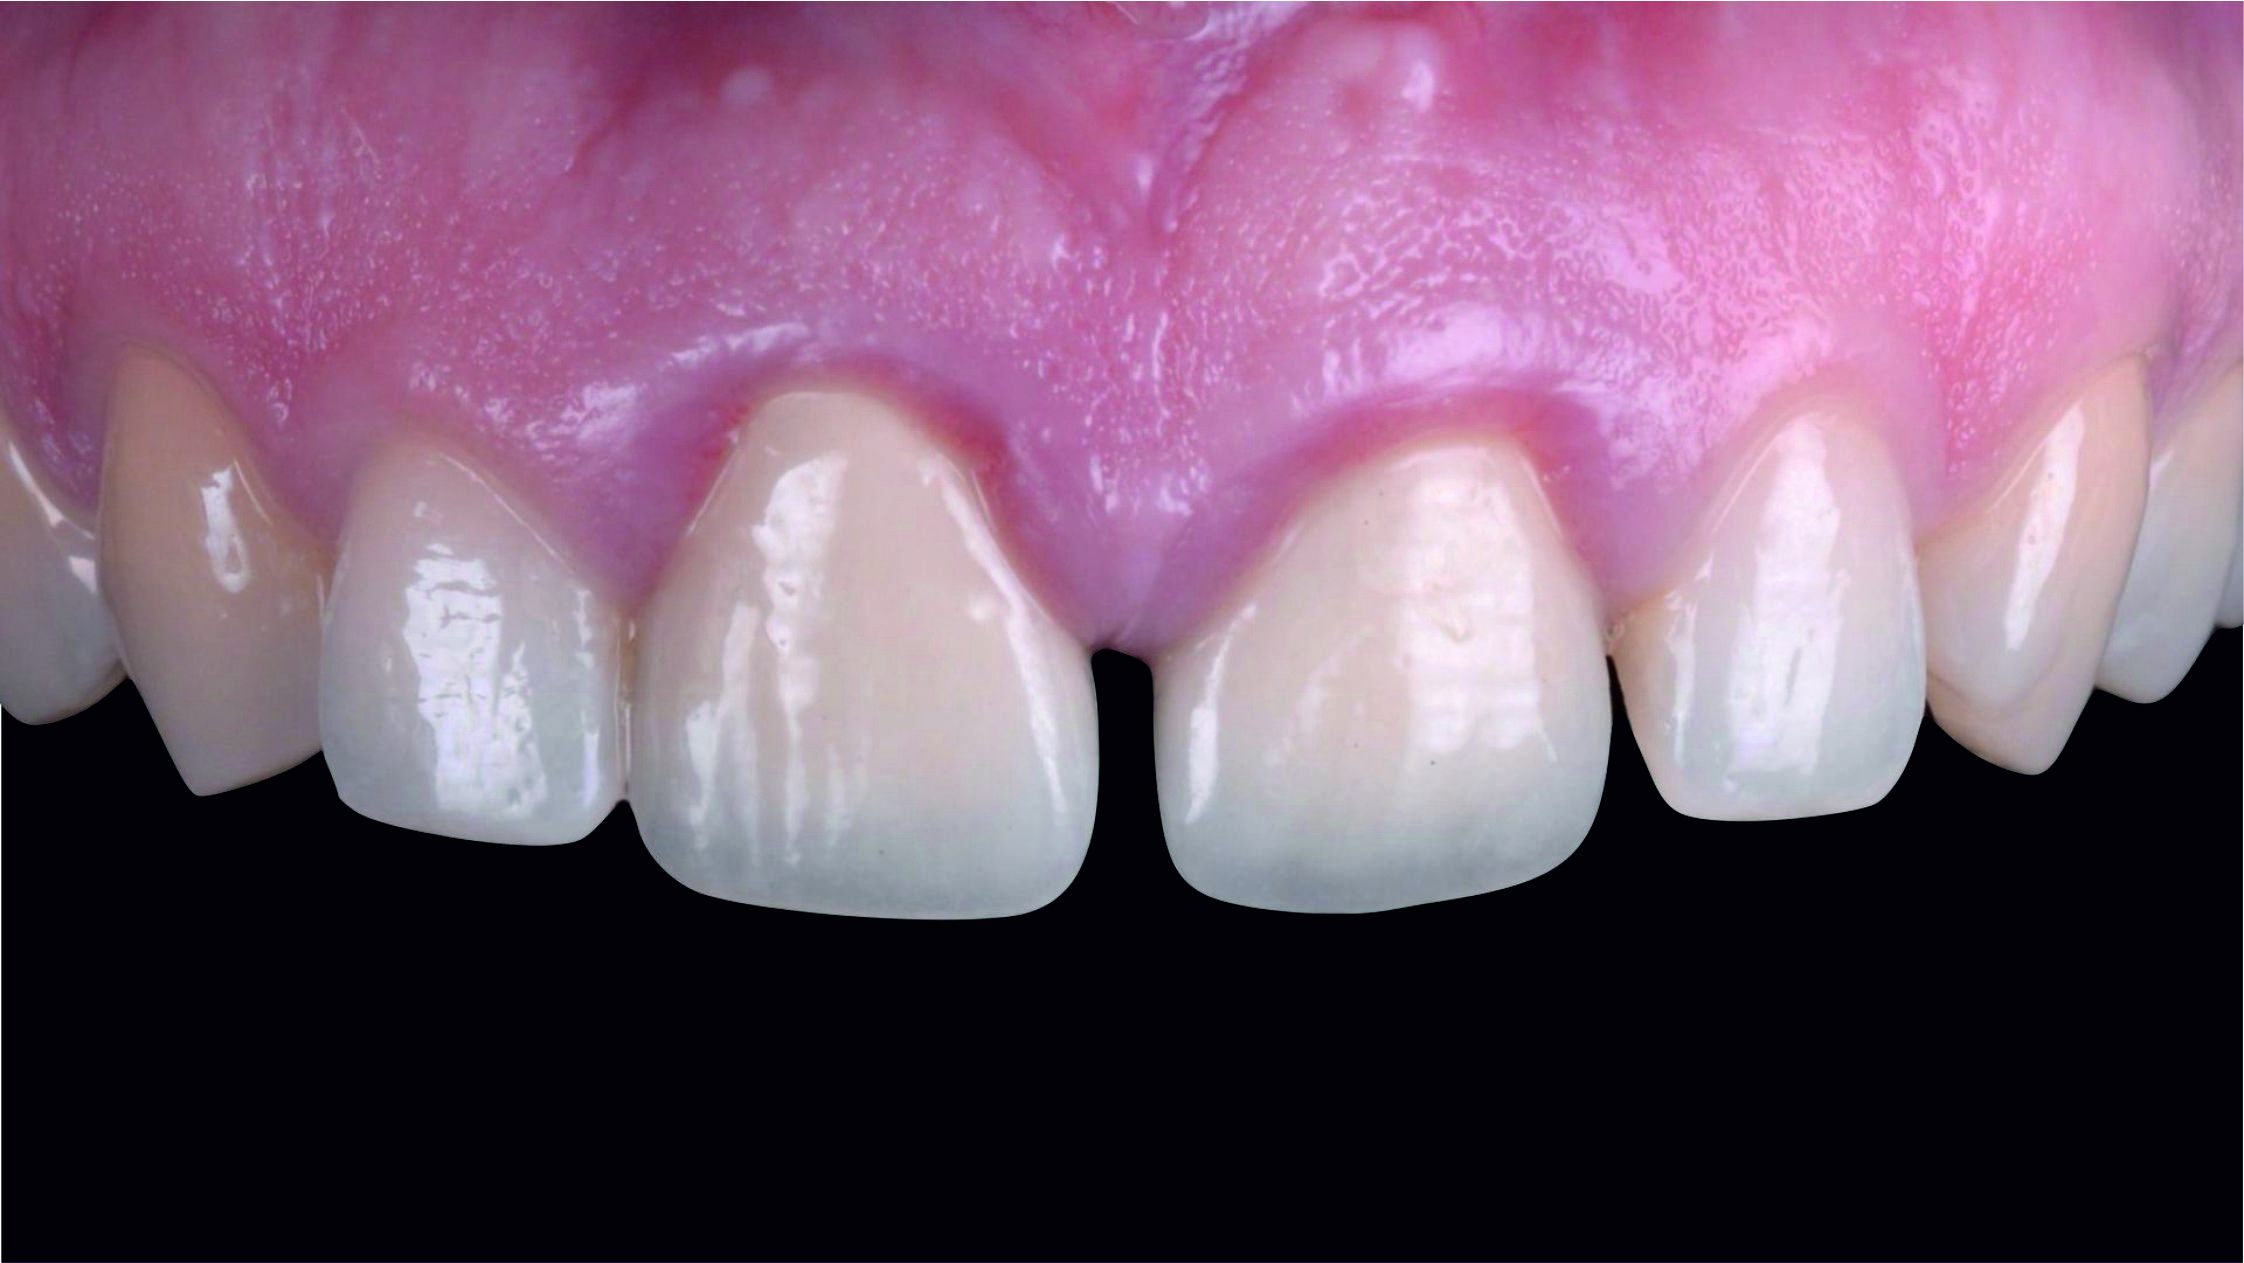

Фото 2. Через високо розташовану лінію посмішки можна припустити, що будь-яка вада після лікування обов'язково буде дуже добре помітною.

Фото 4. Перед тим, як приступити до планування майбутнього естетичного вигляду зубів, необхідно переконатися в тому, що тканини пародонта здорові. Так ми зможемо встановити фактичне розташування рівня зенітів центральних різців.